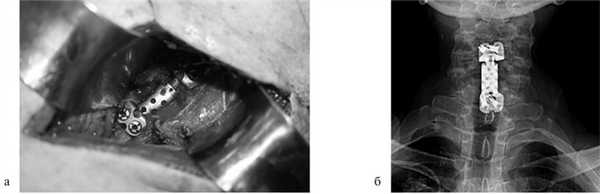

Для замещения удаленных позвонков у 8 (28%) больных применен сетчатый титановый протез «MASH» (рис. 1), который использовался нами с 2006 по 2010 г. Телескопическая система эндопротезирования, которая использовалась с 2010 по 2016 г., применена у 21 (72%) пациента (рис. 2). Спондилодез при помощи пластин выполнен у 19 (65,5%) больных, комбинированная стабилизация (титановые винты и пластины) — у 10 (34,5%) пациентов.

![]()

Рис. 2. Корпорэктомия позвонка СV с замещением дефекта раздвижным эндопротезом тела позвонка. а — интраоперационная фотография; б — послеоперационная рентгенограмма шейного отдела позвоночника.